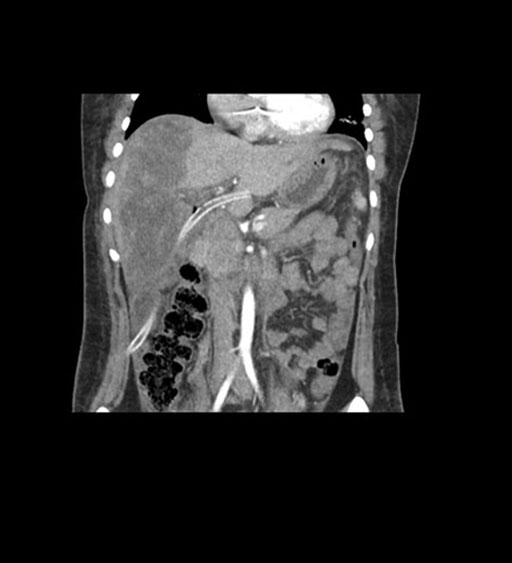

Coronal Arterial

Coronal Venous